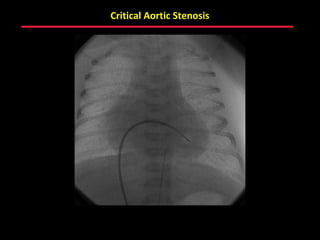

Critical Aortic Stenosis: Aortic Root Injection

Negative contrast jet through

a stenotic aortic valve